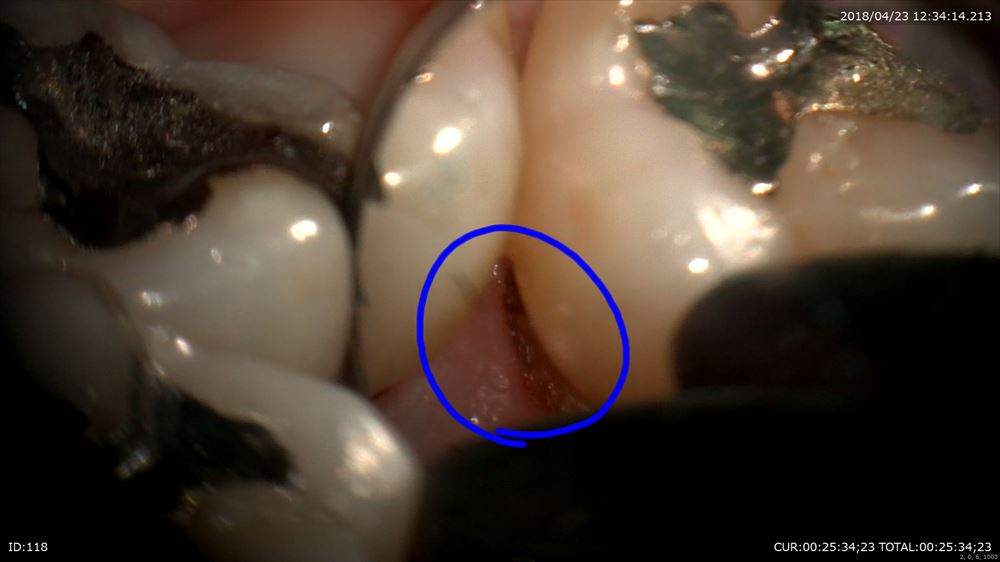

マイクロスコープでポケットの中の歯石(細菌)をみて

秋山勝彦先生ご発明の器具で剥離

この様に歯茎を切らずに歯肉溝からのアプローチ。この器具ミラーの役割もします。

歯根形態がこのように見えるからデブライドメントも、「なんとなく」ではなく歯根にきちっと合わせて行えます。